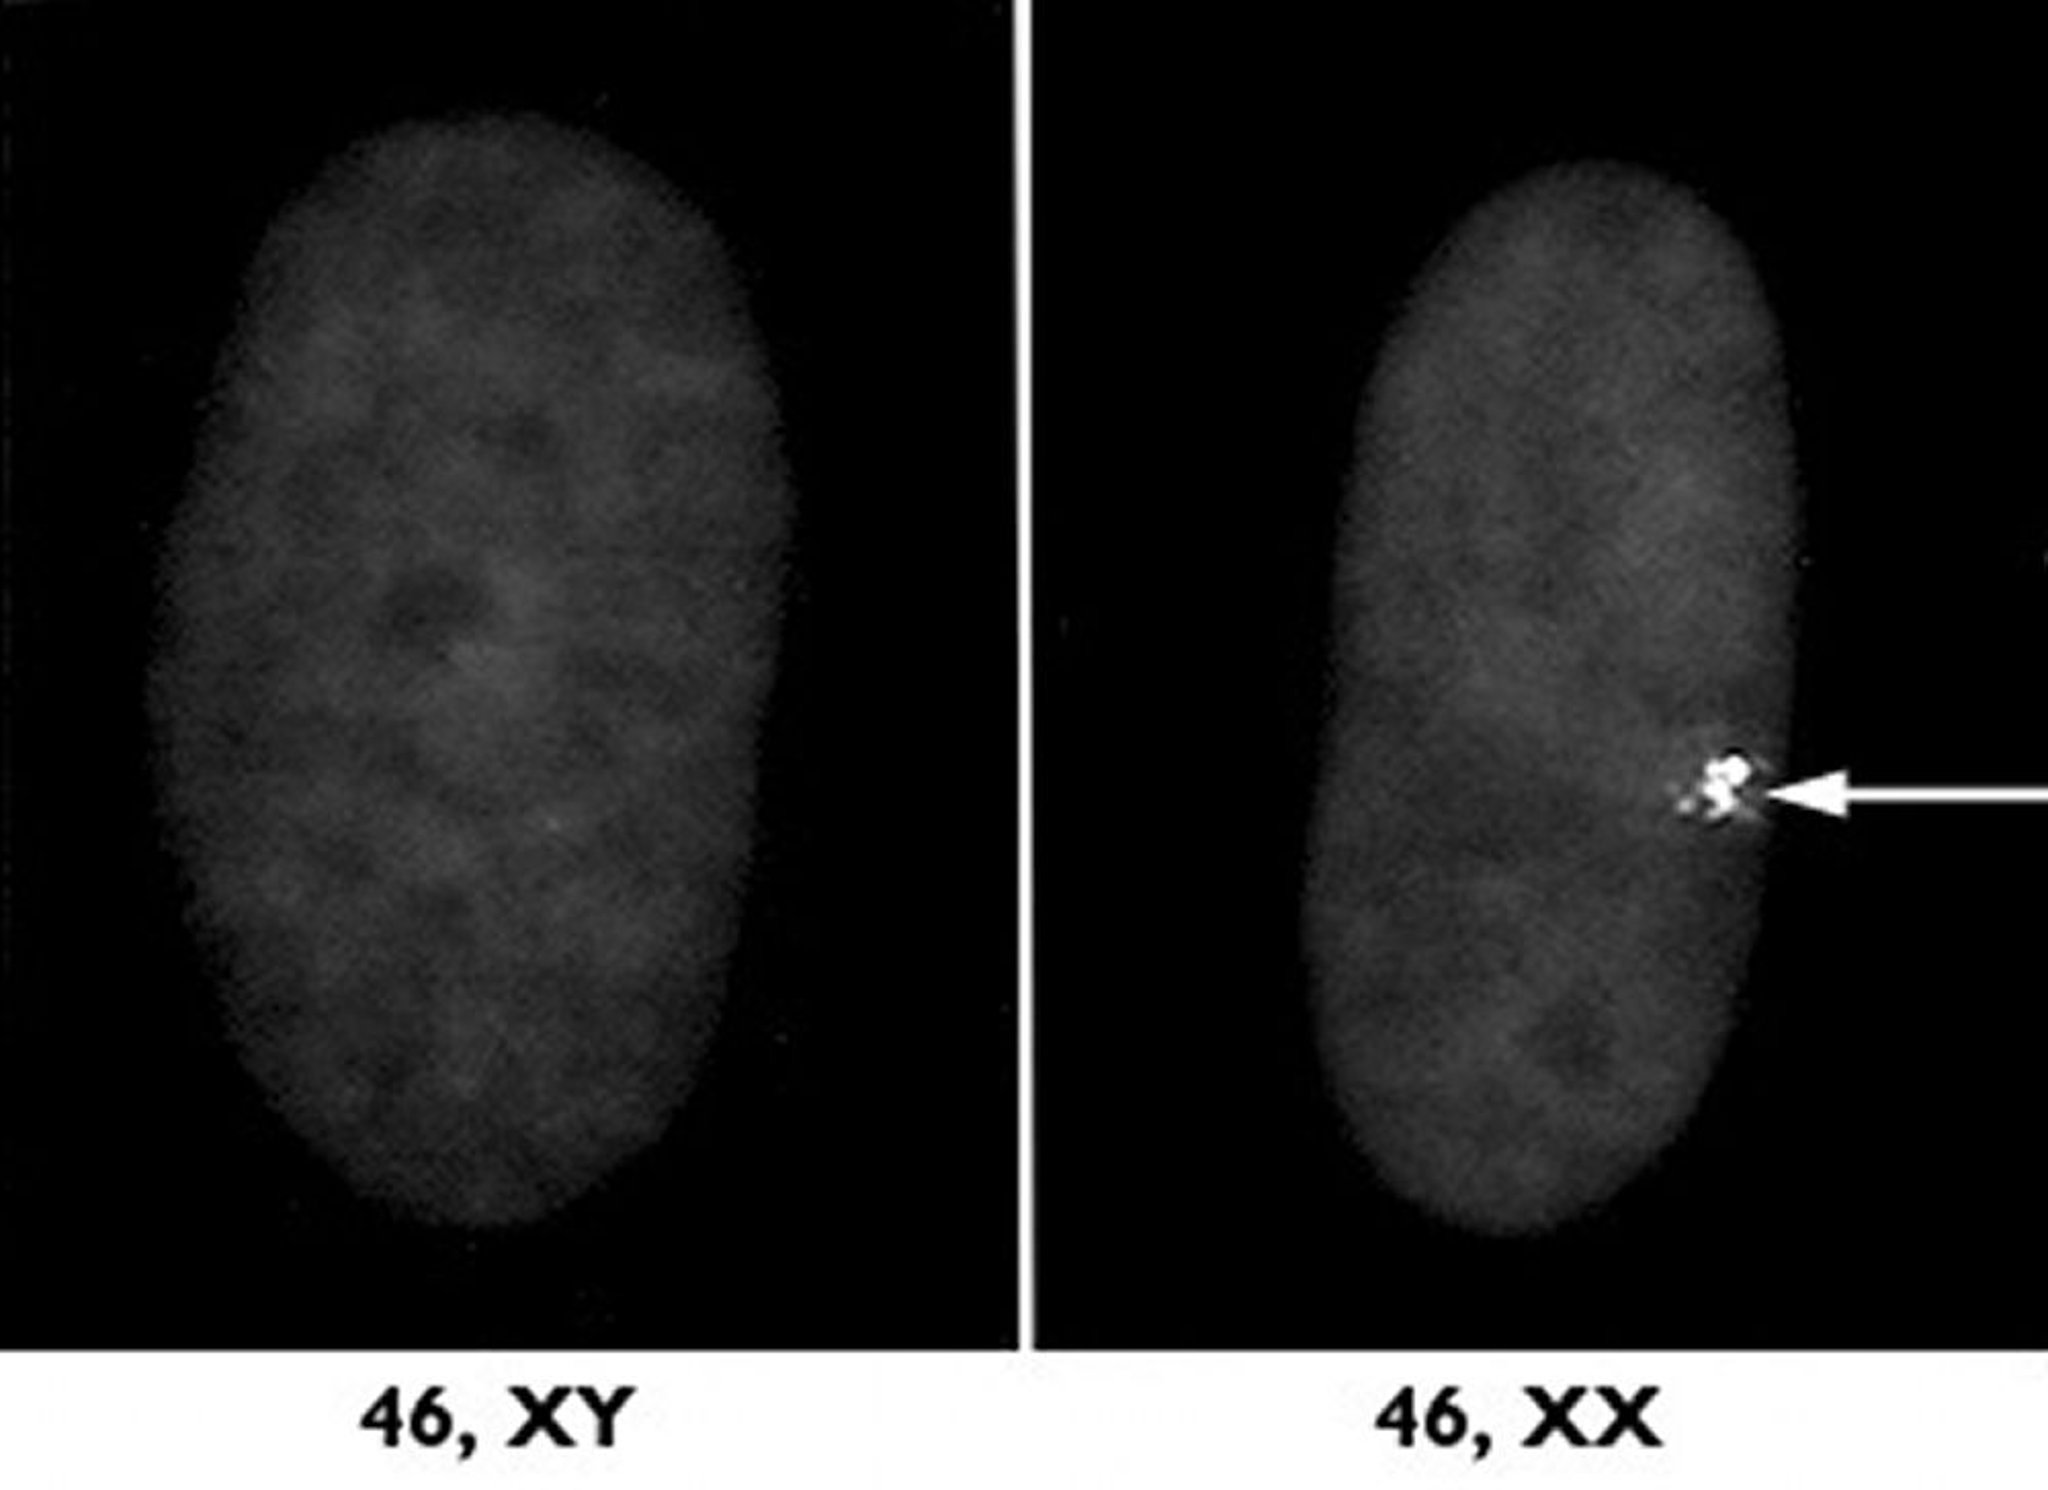

निष्क्रिय X क्रोमोसोम

मादाओं में दो X क्रोमोसोम से एक को X निष्क्रियण नामक प्रक्रिया के माध्यम से बंद कर दिया जाता है। दायीं ओर, मादा से प्राप्त एक कोशिका केंद्रक का अतिसूक्ष्म नमूना है जो इस निष्क्रिय X क्रोमोसोम को एक स्थूल गांठ (तीर का चिह्न) के रूप में दर्शाता है। बायीं ओर, नर से लिया गया एक नमूना है जो तुलना करने के लिए दर्शाया गया है।

डॉक्टर एल. कैरेल एंड एच. विलिअर्ड, केस वेस्टर्न रिज़र्व यूनिवर्सिटी स्कूल ऑफ मेडिसिन के सौजन्य से।